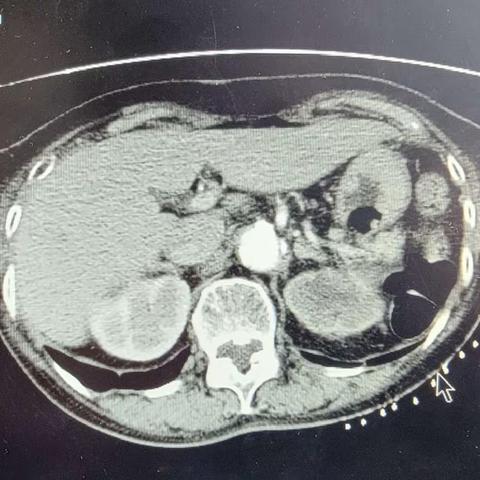

肾盂癌的放射性粒子植入治疗